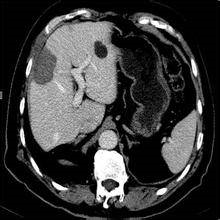

肿瘤射频消融治疗是一种杀伤肿瘤较多而损害机体较轻的肿瘤微创切除治疗方法。肿瘤细胞的特点之一是对热的耐受能力比正常细胞差,该疗法就是根据此特点,应用射频热效应引起组织细胞凝固性坏死的原理而达到消除肿瘤的目的。实施射频消融后,在消融电极的周围形成一个边界清晰近似球形的凝固坏死区,该区域覆盖的肿瘤组织被毁损灭活。凝固坏死的组织部分被人体吸收,这些坏死组织由于其细胞免疫表型的变化而具有瘤苗作用,因此发挥特殊的抗癌作用,并强化患者的免疫功能。

可用于人体器官良、恶性实体肿瘤的治疗,目前临床应用较多的是:肝癌、肾癌、肺癌、肝脏和胸部的转移性肿瘤。对于不能手术切除的上述原发性或者转移性晚期肿瘤、不能承受放疗化疗的实体肿瘤患者,均可接受射频消融治疗。